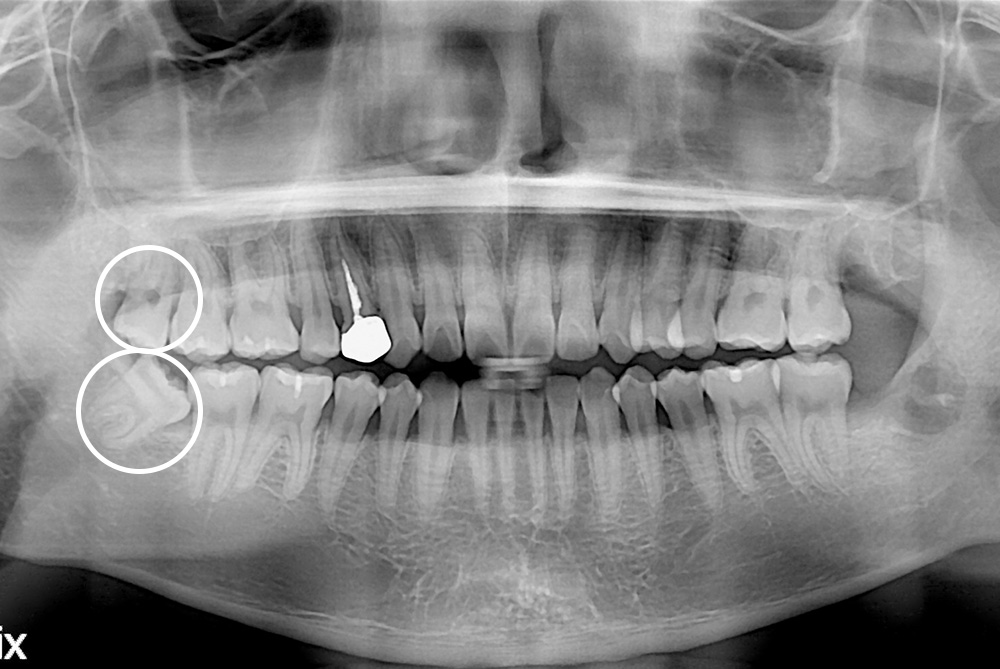

[사랑니] 매복 사랑니 발치

치료후 : 2016-03-29

세종치과는 구강악안면외과학 박사이신 원장님이 발치하는 치과입니다.